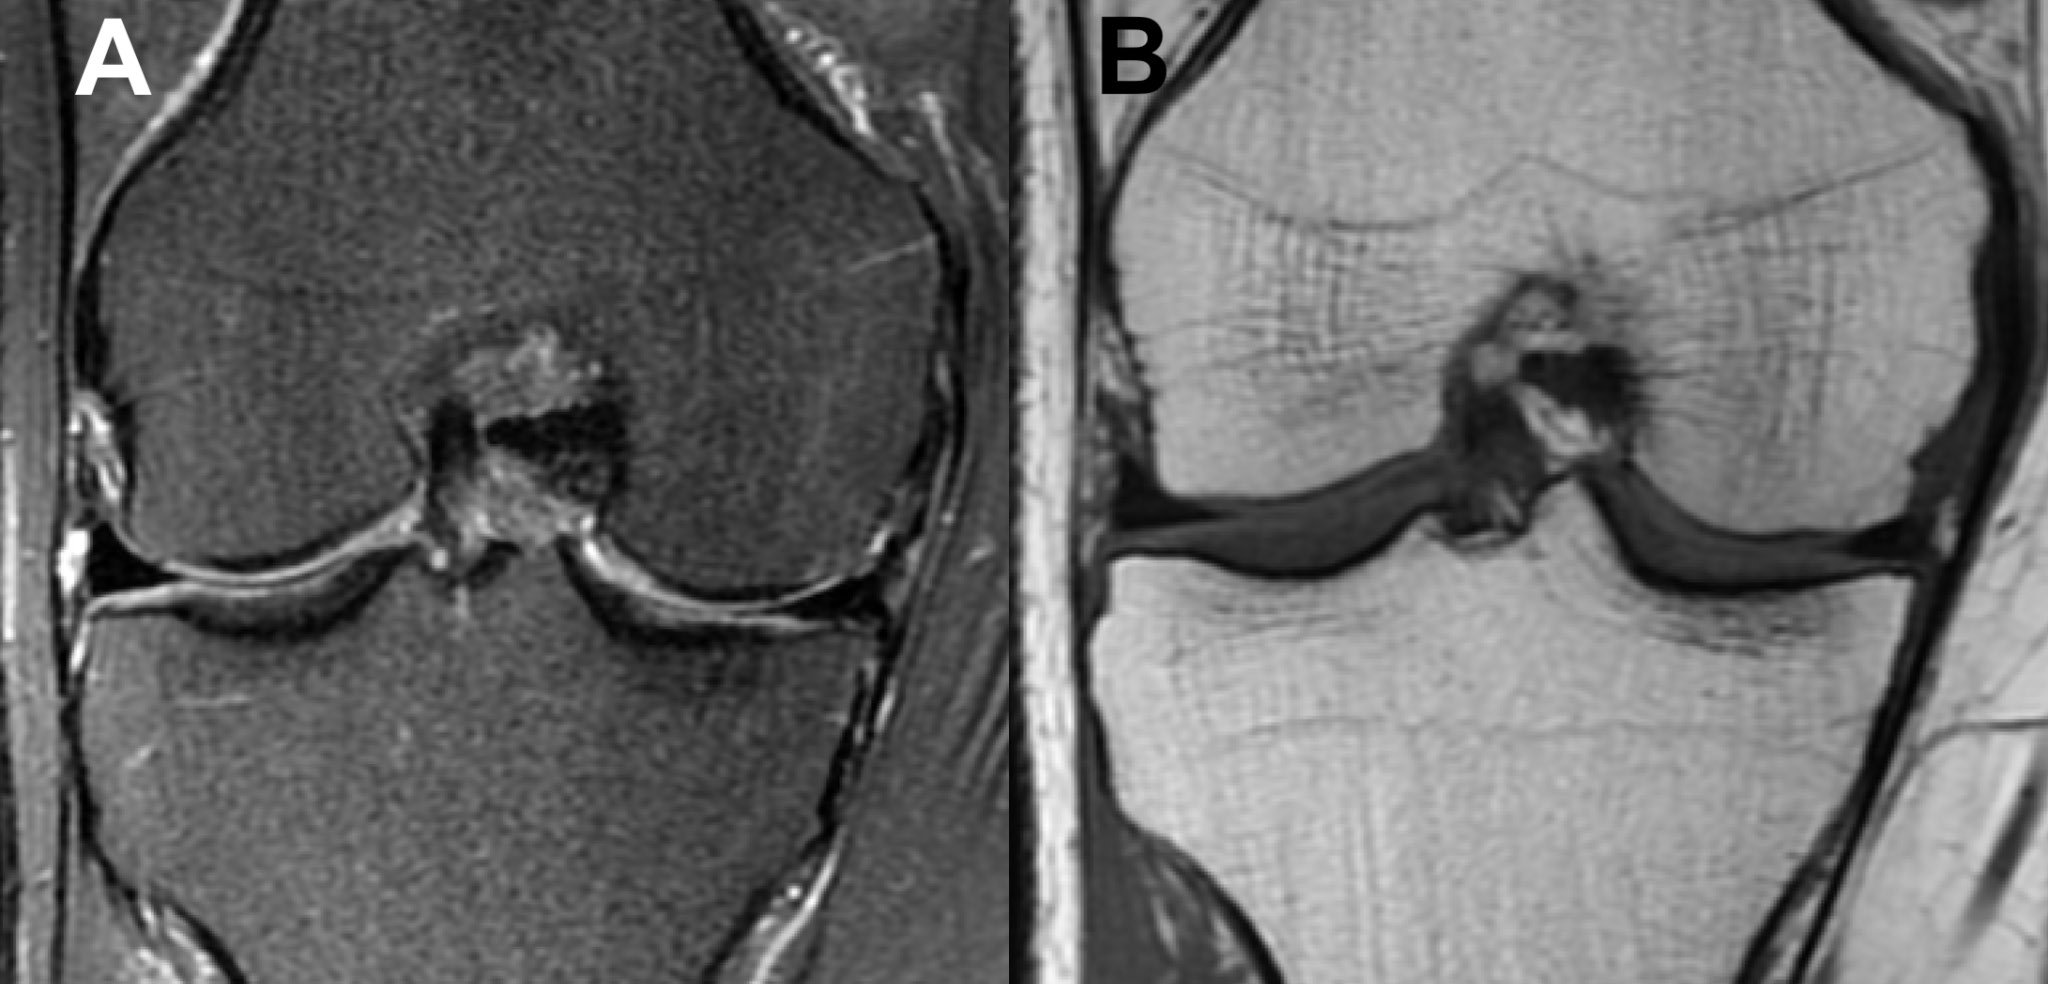

The 2 cases of PCT-SONK presented in this study add to the differential diagnosis of sudden knee pain in uninjured patients during the ongoing pandemic. It is particularly noteworthy that the radiological findings that constitute PCT-SONK, although similar in both cases presented in this study, are radiologically distinct in appearance from classic SONK (Figure 6). No subchondral bone thickening was observed, and the bone edema was more diffuse in the whole femoral condyle, in contrast to focal edema, which is concentrated mainly around the subchondral region and typically observed in classic SONK (Table 1).

Fig. 5. Follow-up magnetic resonance imaging (MRI) coronal view of the right knee (Case 2) performed after the resolution of symptoms. The signal in the medial femoral condyle in both (A) short tau inversion recovery (STIR) fast spin echo (FSE) and (B) longitudinal relaxation time (T1) sequences is almost normal. It is noteworthy that there is no visible soft tissue edema

Fig. 6. Radiological (coronal magnetic resonance imaging (MRI) views) appearance of classic spontaneous osteonecrosis of the knee (SONK) in the right knee. There is a focal signal increase in subchondral bone in both (A) short tau inversion recovery (STIR) fast spin echo (FSE) and (B) proton density (PD) magnetic resonance imaging (MRI) sequences